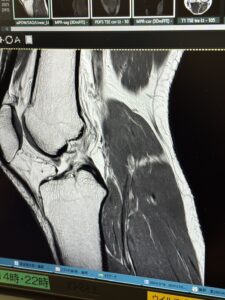

AI診断🦵

次女のOPEは無事終了したようです。病名:前十字靭帯損傷 手術名:関節鏡下前十字靭帯再建&

半月板縫合 だそうです。う〜んどこが損傷かわからないな〜、ということで

AI診断すると1発で病変部位を教えてくれました。まさに医者いらずですね。やばい😨